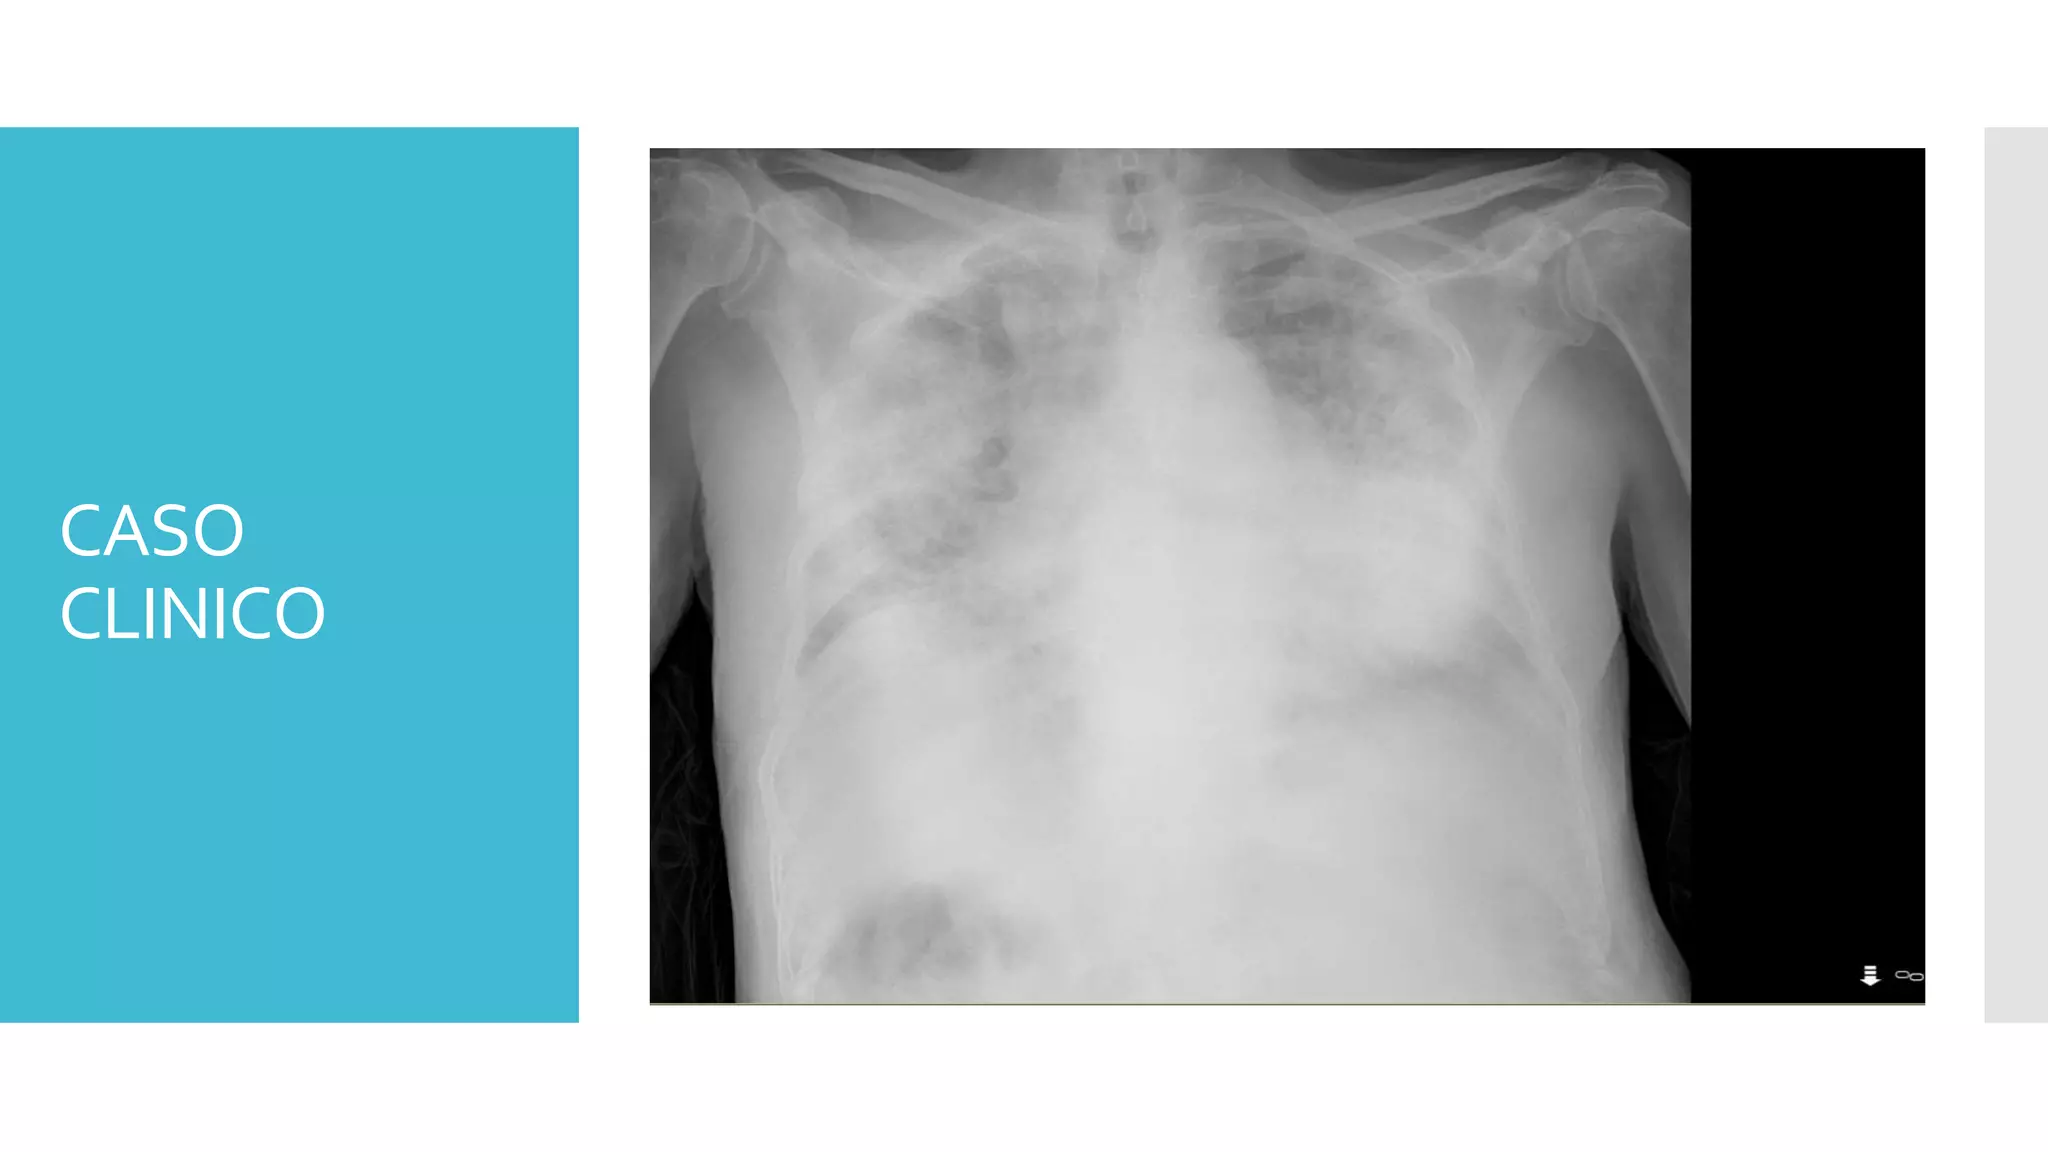

CASO

CLINICO

Anamnesis:

Varón 82 años, independiente para ABVD, acude a Urgencias por astenia y

disnea de 24 horas de evolución. Dado de alta del servicio de Geriatría del

Hospital Militar hace 3 días por NAC.

No fiebre termometrada en domicilio.

Tos con escasa expectoración de 48 horas de evolución.

No dolor torácico ni palpitaciones.

Ortopnea y aumento de disnea hasta hacerse de minimos esfuerzos las

últimas 24 horas junto con astenia intensa y empeoramiento del estado

general.

No otra sintomatología.

AP: miocardiopatía dilatada, ACXFA, HTA, DLP, pancreatitis aguda litiasica

en 2017

IQ: colecistectomía, hernioplastia inguinal derecha

Tto actual: atorvastatina 40 0-0-1, pantoprazol 20 1-0-0, apixaban 5 1-0-1,

carvedilol 6,25 ½-0-1/2, ramipril 2,5 ½-0-0, furosemida 40 1-0-0,

paracetamol si precisa

CLINICO Exploración física:

Consciente y orientado, regular estado general, palidez,

normohidratado, GCS 15

AP: crepitantes en ambas bases pulmonares con hipoventilación

generalizada

AC: tonos rítmicos y sin soplos

Abdomen: blando y depresible, no se palpan masas ni

visceromegalias, no signos de irritación peritoneal, puño percusión

renal negativa bilateral

EEII: edemas maleolares, pulsos pedios presentes y simétricos

Constantes vitales:

TA 92/47, FC 86,Tª 36.7ºC, Sat O2 94% reservorio

 Orientación diagnóstica: neumonía nosocomial vs NAC con mala

evolución pese a tratamiento vs reagudización de insuficiencia

cardiaca

 PC:

 AS

 BQ, PCR, GASOMETRIA ARTERIAL, HEMOGRAMA, COAGULACION

 ProBNP

 AO

 RXTORAX

 ECG

 TRATAMIENTO INICIAL:

 SF 500 mantenimiento

 O2 con reservorio

 RESULTADOS PRUEBAS COMPLEMENTARIAS:

 ECG: ACXFA a 78 lpm

 AS:

 GASOMETRIAARTERIAL: pH 7,48, pCO2 35,3, HCO3 25,7 , lactato

 PCR: 4,84

 ProBNP (757,6, previo 1700)

 BQ: glu 102, creat 0,63 (previa 1,10), urea 32, cl 108, Na 134, K 4,6

 HEMOGRAMA: 20,000 leucocitos (17800 neutrófilos), Hb 10,8, Hto 33,6,

plaquetas 201.000

 COAGULACION: INR 1,18, act protrombina 78%, fibrinógeno derivado 3,6

 AO: sin alteraciones

 RX.TÓRAX: progresión de las áreas de consolidación pulmonar bilaterales, no

derrame pleural, cardiomegalia

Ante la sospecha de sepsis y el empeoramiento del paciente, se extraen

hemocultivos, angtigenos en orina de neumococo y legionella, se realiza

nueva carga de SF 500 y se inicia antibioterapia IV con levofloxacino